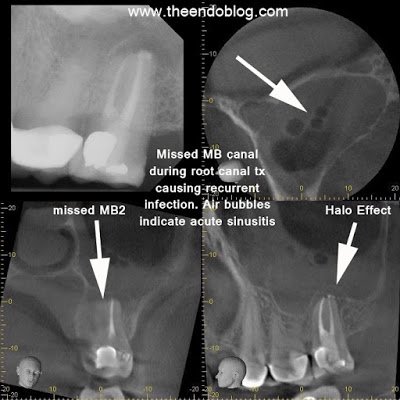

CBCT (J. Morita Veraviewepocs 3De) demonstrates a large periapical radiolucency around the buccal roots of #15. The sagittal view shows elevation in the floor of the sinus (halo effect). Coronal view shows arrow pointing to a missed mesio-buccal canal causing the endodontic infection. Air bubbles seen in the maxillary sinus are indicative of an acute sinusitis. Endodontic retreatment is required BEFORE sinus treatment. Failure to address the odontogenic source of the sinus infection will result in recurrent sinus infections.